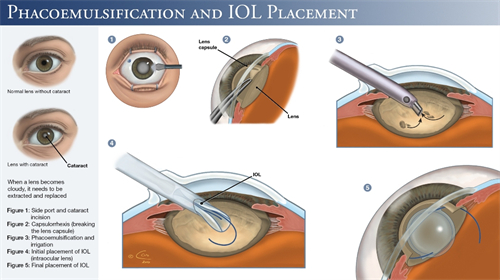

在白内障手术技术迭代浪潮中,艾无极人工晶体凭借“一术多效”的连续视程技术,成为中高端患者群体的热门选择。

作为强生眼力健基于TECNIS平台研发的第三代无级变焦晶体,它突破传统单焦点、多焦点晶体的局限,通过创新光学设计实现远中近视力无缝衔接,同时覆盖近视、散光、老花眼矫正需求。

手术费用涵盖超声乳化技术、飞秒激光辅助等选项。

单次手术同步解决白内障、近视、散光、老花眼四大问题,术后脱镜率较高。

五、技术迭代:从实验室到临床的突破

光学建模突破:

通过***光线追踪模拟,优化晶体前表面曲率,实现焦深延长。

临床验证体系:

国内外多中心研究纳入患者,术后随访显示中距离视力提升。

手术操作便捷性:预装式设计缩短手术时间。